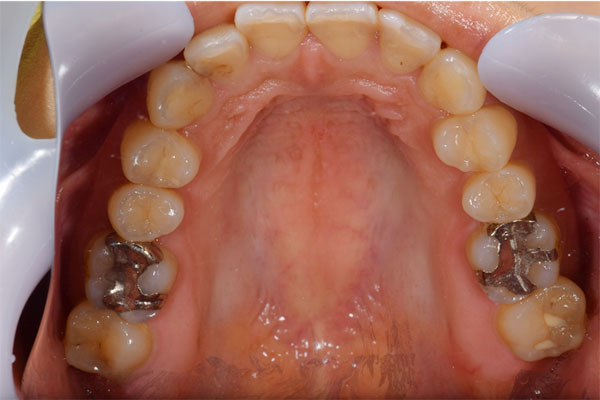

【担当医師所見】

左下奥歯は親知らずが原因でクラウン(かぶせ物)の下まで虫歯になっています。 またその手前の歯は根中央部に大きな透過像(黒い像)が見られます。クラウン除去後、マイクロスコープ下で確認したところ中央部は亀裂が入り保存不可能な状態になっており抜歯となりました。

右上の銀歯の下にあった虫歯は大きかったものの歯の神経を残すことがなんとかできたので部分的なセラミックのつめ物(セラミックインレー)での治療となりました。

また反対側の奥歯も古くなっており、将来性を考えセラミックへ変更しています。